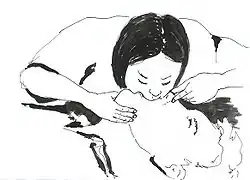

First aid for choking infants alternates a cycle of special back blows (five back slaps) followed by special chest thrusts (five adapted chest compressions).

In the back blows maneuver, the rescuer slaps on the baby's back. It is recommended that the baby receive them being slightly leaned upside-down on an inclination. There exist several ways to achieve this:

According to a widely propagated modality: the rescuer sits down on a seat with the baby, and supports the baby with a forearm and its respective hand. The baby's head must be carefully held with that hand (approximately by the face), and kept in a normal position, facing forward, not inclinated. Then the baby's body can be leaned forward upside-down along the rescuer's thighs, and receive the slaps.

As an easier alternative: the rescuer can sit on a bed or sofa, or even the floor, carrying the baby. Next, the rescuer should support the baby's body on the own lap, to lean the baby a bit upside-down at the right or the left of the lap. The baby's head must be in a normal position, facing forward, frontally, and not inclinated. It is always convenient that the baby's chest is supported against something. Then the rescuer would slap the back of the baby.

If the rescuer cannot sit down: at least it is possible to attempt the manoeuver at a low height and over a soft surface. Then the rescuer would support the baby with a forearm and the hand of that side, holding carefully the baby's head with that hand (approximately by the face, but always trying that the baby's head keeps in a normal position, facing forward, not inclinated). The baby's body would be leaned upside-down in that position to receive the slaps. In situations with rescuers who cannot do all of that (as rescuers with disabilities and others), they can still try the normal back blows, supporting the baby's chest with one hand, bending the baby's body, and then giving firm slaps with the other hand.

In the chest thrusts manoeuver, the baby's body is placed lying face up on a surface (it can be the rescuer's thighs, lap or forearm). Then, the rescuer does the compressions pressing with only two fingers on the lower half of the bone that is along the middle of the chest from the neck to the belly (on the chest bone, named sternum, on its part that is the nearest to the belly). Abdominal thrusts are not recommended in children less than one year old because they can cause liver damage.[60]

The back blows and chest thrusts are alternated in cycles of five back blows and five chest compressions until the object comes out of the infant's airway or until the infant becomes unconscious.[60]